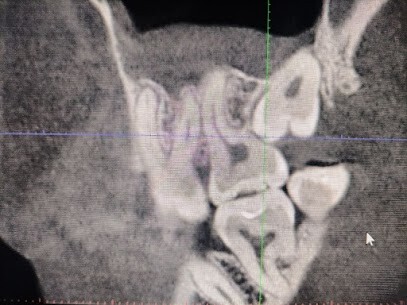

Прорезавшиеся зубы мудрости, или третьи моляры, нередко становятся причиной дискомфорта и проблем со здоровьем ротовой полости. Если вы ощущаете боль в области задних зубов, замечаете воспаление десен или испытываете затруднения при открывании рта, это может быть сигналом к визиту к стоматологу.

Удаление зуба мудрости – распространенная процедура, которая может быть рекомендована в различных случаях. Это может быть неправильное положение зуба, недостаток места в челюсти, приводящий к давлению на соседние зубы, или развитие кариеса в труднодоступной области.